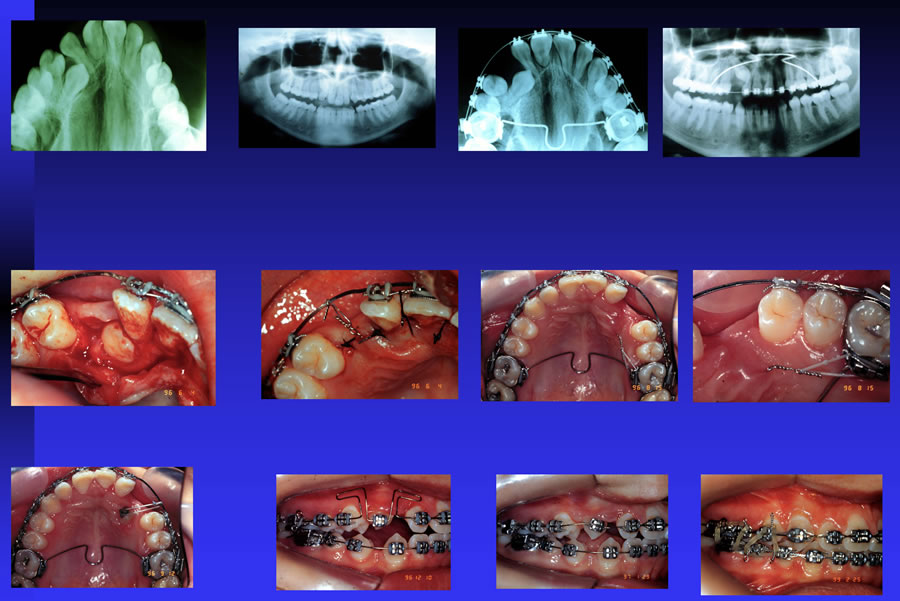

Nesses casos, faz-se necessário um exame radiográfico detalhado dos ossos para avaliar a posição exata do dente. Em alguns casos, pode ser necessário, até mesmo, a utilização da tomografia computadorizada.

Normalmente, o paciente fica inicialmente em torno de 1 ano com o aparelho fixo a fim de fazer o alinhamento inicial.

Após essa fase, faz-se uma exposição cirurgia do dente com um cirurgião Bucomaxilofacial, onde um acessório (botão metálico) é colado no dente a fim de permitir o seu tracionamento. O tempo para o tracionamento do dente é imprevisível e pode durar no mínimo 6 meses. Após o tracionamento, segue-se o tratamento ortodôntico a fim de acertar a oclusão (mordida) e o alinhamento dos dentes.